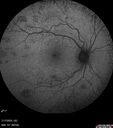

Traumatic Peripapillary Subretinal Hemorrhage2 views16 year old hit in eye with finger during basketball. Vision is 20/25 and there is a peripapillary hemorrhage.Apr 13, 2026